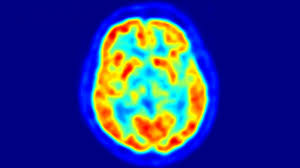

LE 3 NOSTRE AREE ATTUALI DI RICERCA sono , dice il il Prof. Michele Fonti Psichiatra

AREA DI RICERCA PSICHIATRICA: "TERAPIA SINCRONO-SEQUENZIALE NEI PAZIENTI RESISTENTI ALLE CURE FARMACOLOGICHE E PSICOLOGICHE"

AREA DI RICERCA DI NEUROIMAGING: “MODIFICAZIONI NEUROFUNZIONALI NELLA MENZOGNA PATOLOGICA”

AREA DI RICERCA DI ETNOPSICOLOGIA/PSICHIATRIA: IMPATTO DEL SOGGETTO NARCISISTICO NELLE STRUTTURE DI CONTROLLO E POTERE : CONSEGUENZE NEL SISTEMA SOCIALE DELLA CORRUZIONE